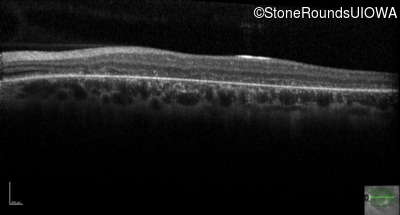

Optical Coherence Tomography - Left - 20/200 -2

Exemplar / OCT Stack